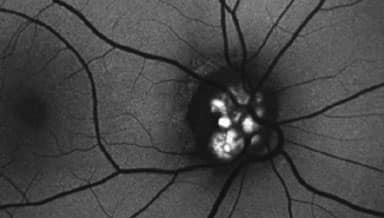

Fundus Autofluorescence (FAF)

Fundus Autofluorescence (FAF) is a non-invasive retinal image providing information on retinal metabolism and function. It is especially useful in assessing optic nerve head drusen and retinal maculopathies like macular degeneration.